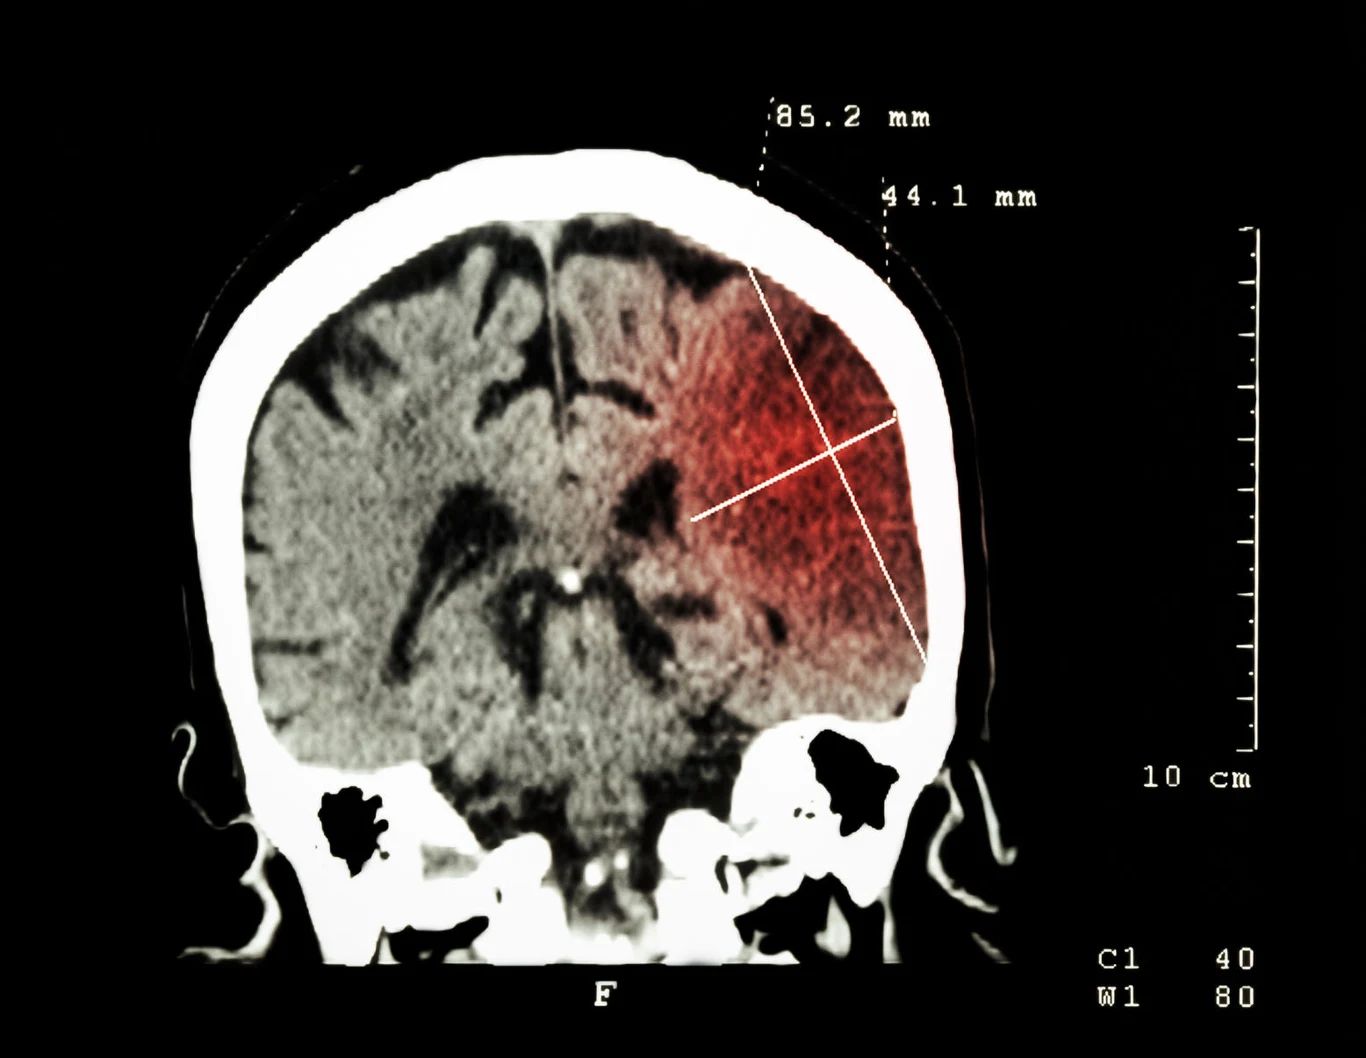

Zespół Lydena zauważył, że lekarze zgłaszają zaskakującą liczbę poważnych udarów mózgu u pacjentów cierpiących na COVID-19. Związek między chorobami nie jest jednak jasny. Wielu pacjentów miało nadciśnienie tętnicze i cukrzycę, które stawiają ich w grupie ryzyka. Może to oznaczać, że koronawirus przyczynia się do wystąpienia udaru u osób z grupy ryzyka.Istnieją także podejrzenia, że infekcja SARS-CoV-2 może być przyczyną zwiększonej krzepliwości krwi, która stanowi bezpośrednią przyczynę udaru. Istnieją doniesienia o udarach mózgu u stosunkowo młodych pacjentów z COVID-19.- Widziałem to na własne oczy - zdrowi młodzi ludzie z COVID-19 także dostają udarów. Musimy być czujni. Wygląda na to, że są obserwacje, które powinny martwić wielu z nas, ale nie jestem gotów powiedzieć, że wiemy, o czym mówimy - powiedział prof. Lyden.Dr Thanh Nguyen z Bostońskiego Centrum Medycznego, profesor neurologii, neurochirurgii i radiologii w Szkole Medycznej Uniwersytetu Bostońskiego, zgodziła się, że dopóki dowody nie będą silniejsze, nie można wiązać COVID-19 z udarem mózgu. Prof. Nguyen powiedziała, że u pacjentów z COVID-19, u których doszło do udaru mózgu, występowały typowe naczyniowe czynniki ryzyka, takie jak nadciśnienie tętnicze, cukrzyca i migotanie przedsionków.